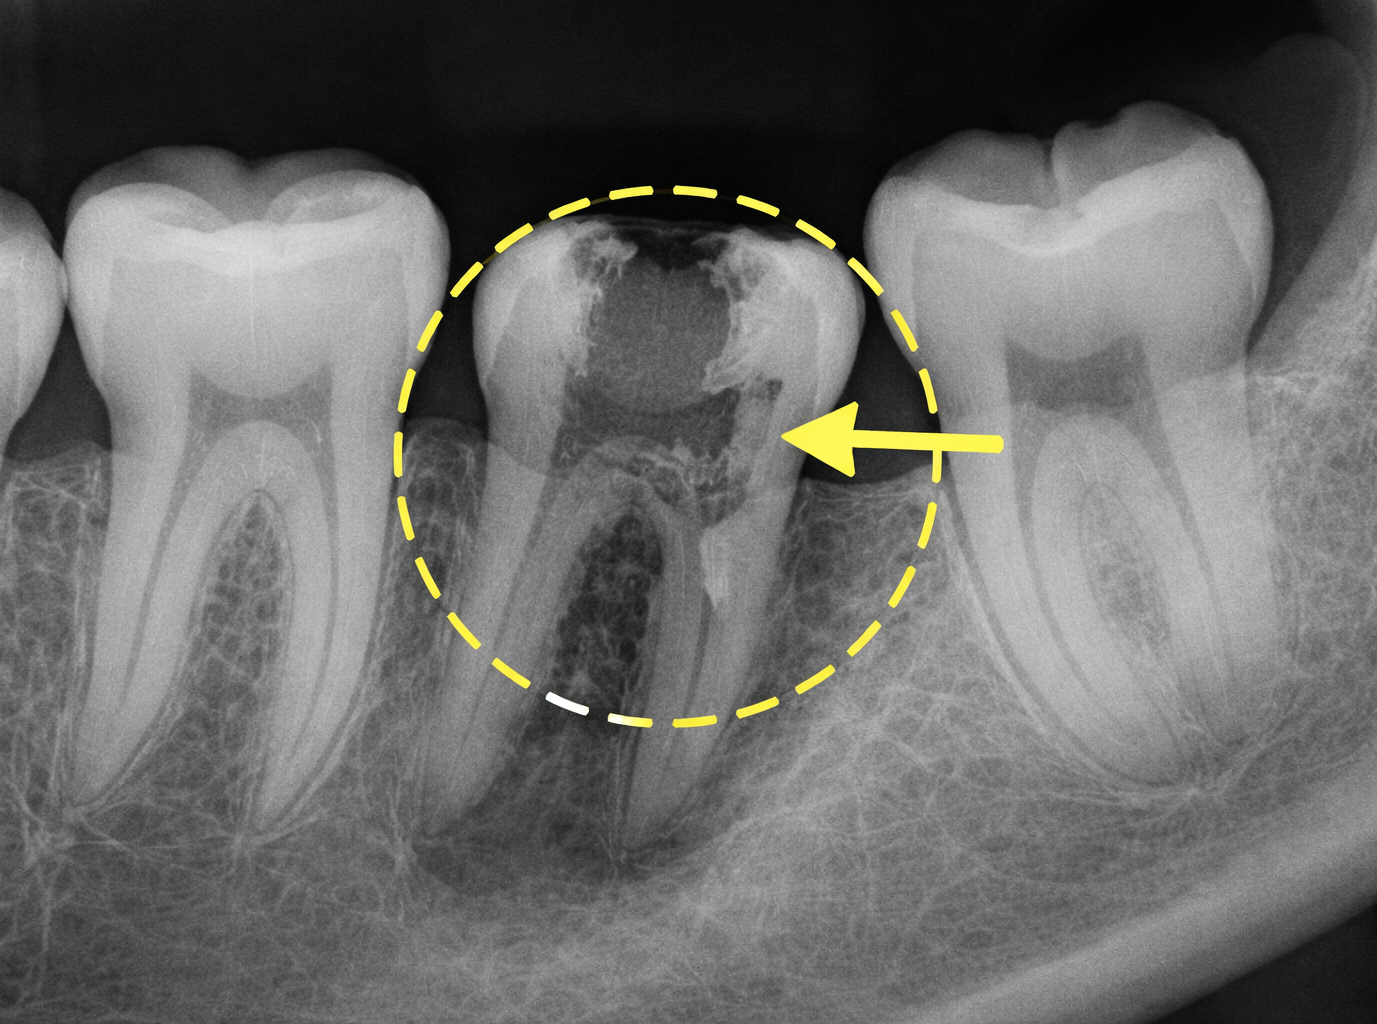

Before recommending an extraction, we carefully evaluate the tooth and surrounding bone using X-rays, paying close attention to root shape and anatomy to identify any curves or hooks that could affect the procedure. We also review your medical history to ensure the approach is safe and appropriate for you. When removal is the best option, we plan the procedure thoughtfully to minimize trauma and support smooth, predictable healing.